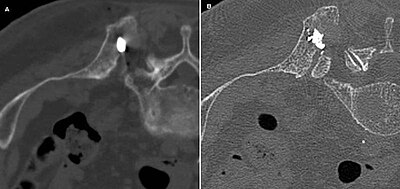

Will a CT scan show arthritis?

For people with arthritis, CT is typically used for examining joints that are deep in the body and difficult to assess with conventional x-ray, especially in the spine or pelvis.